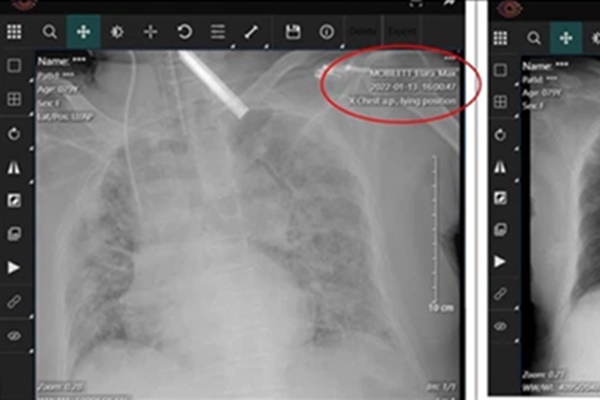

Bệnh nhi N.P. được chăm sóc tại Bệnh viện Tim Hà Nội. Ảnh: BVCC.

Sau khi nhập viện, bệnh nhi được sơ cấp cứu và chuyển tới khoa Hồi sức Nhi để đặt nội khí quản. Dẫu vậy, tình trạng của bé vẫn diễn biến xấu, chỉ số thở máy cao, huyết động không ổn định.